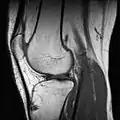

| Magnetic resonance imaging (MRI) alias Nuclear magnetic resonance (NMR) | high strength (0.15 to 1.5 teslas)[4] are used to excite protons that produce the record results (like CT scan). It can show particular tissues more clearly than CT.;[4] video link |